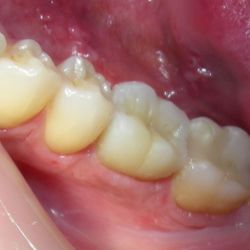

Η νεαρή αυτή ασθενής προσήλθε στο ιατρείο με κάταγμα του παρειακού φύματος του άνω αριστερού προγομφίου.

Το δόντι είχε υποστεί απονεύρωση. Προκειμένου να διαφυλαχθεί η δομική ακεραιότητα του υπολοίπου δοντιού, αποφασίστηκε να αποκατασταθεί το δόντι με εργαστηριακή επένθετη έμφραξη σύνθετης ρητίνης με ελάχιστη αποκοπή οδοντικής ουσίας.

Διατηρήθηκε έτσι ακέραιο το δόντι ενώ η αισθητική του αποκαταστάθηκε απόλυτα.